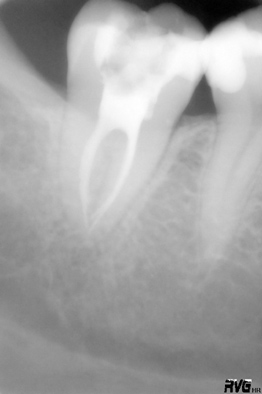

Die Endodontie oder Endodontologie ist der Bereich der Zahnmedizin, der sich mit den Erkrankungen des Zahnmarkes bzw. Zahnnervs beschäftigt. Durch Karies oder Zahnfraktur infizierte oder bereits abgestorbene Zahnnerven müssen entfernt werden. Unter örtlicher Betäubung wird das Wurzelkanalsystem des Zahnes mechanisch und chemisch gereinigt. Die mechanische Aufbereitung erfolgt mit winzig kleinen Feilen als Handinstrumenten oder durch maschinelle Aufbereitung. Vor allem bei engen und stark gebogenen Wurzelkanälen hat sich moderne maschinelle Aufbereitungstechniken bewährt. In unserer Praxis arbeiten wir dabei mit den Feilen des VDW-Reciproc/ReciprocBlue-Systems, welche aus einer hoch flexiblen Titan-Legierung bestehen. Die chemische Reinigung und Desinfektion erfolgt mit Spüllösungen aus Natriumhypochlorid und EDTA mit Ultraschallaktivierung derselben. Abgefüllt wird das Kanalsystem mit einem thermoplastischen Füllverfahren mit warmer Guttapercha, welche mit einem hoch gewebsverträglichen Sealer im Kanal verklebt wird. Die Füllmethode ist medikamentenfrei, d.h. ohne dauermedikamentösen Zusatz!

Anzumerken ist, dass nur nach vollständiger Aufbereitung und gründlicher Desinfektion des Kanalsystems sowie dichter dreidimensionaler Füllung desselben ein langfristiger Behandlungserfolg möglich ist. Grundsätzlich muss jedoch klar sein, dass jede Wurzelbehandlung nur einen Behandlungsversuch darstellt, der jedoch in den allermeisten Fällen eine gute Prognose hat.

Der wurzelbehandelte Zahn ist in vielen Fällen nicht mehr einfach durch eine neue Füllung zu versorgen, sondern muss oft in der Folge überkront werden, um seinen langfristigen Erhalt zu sichern.